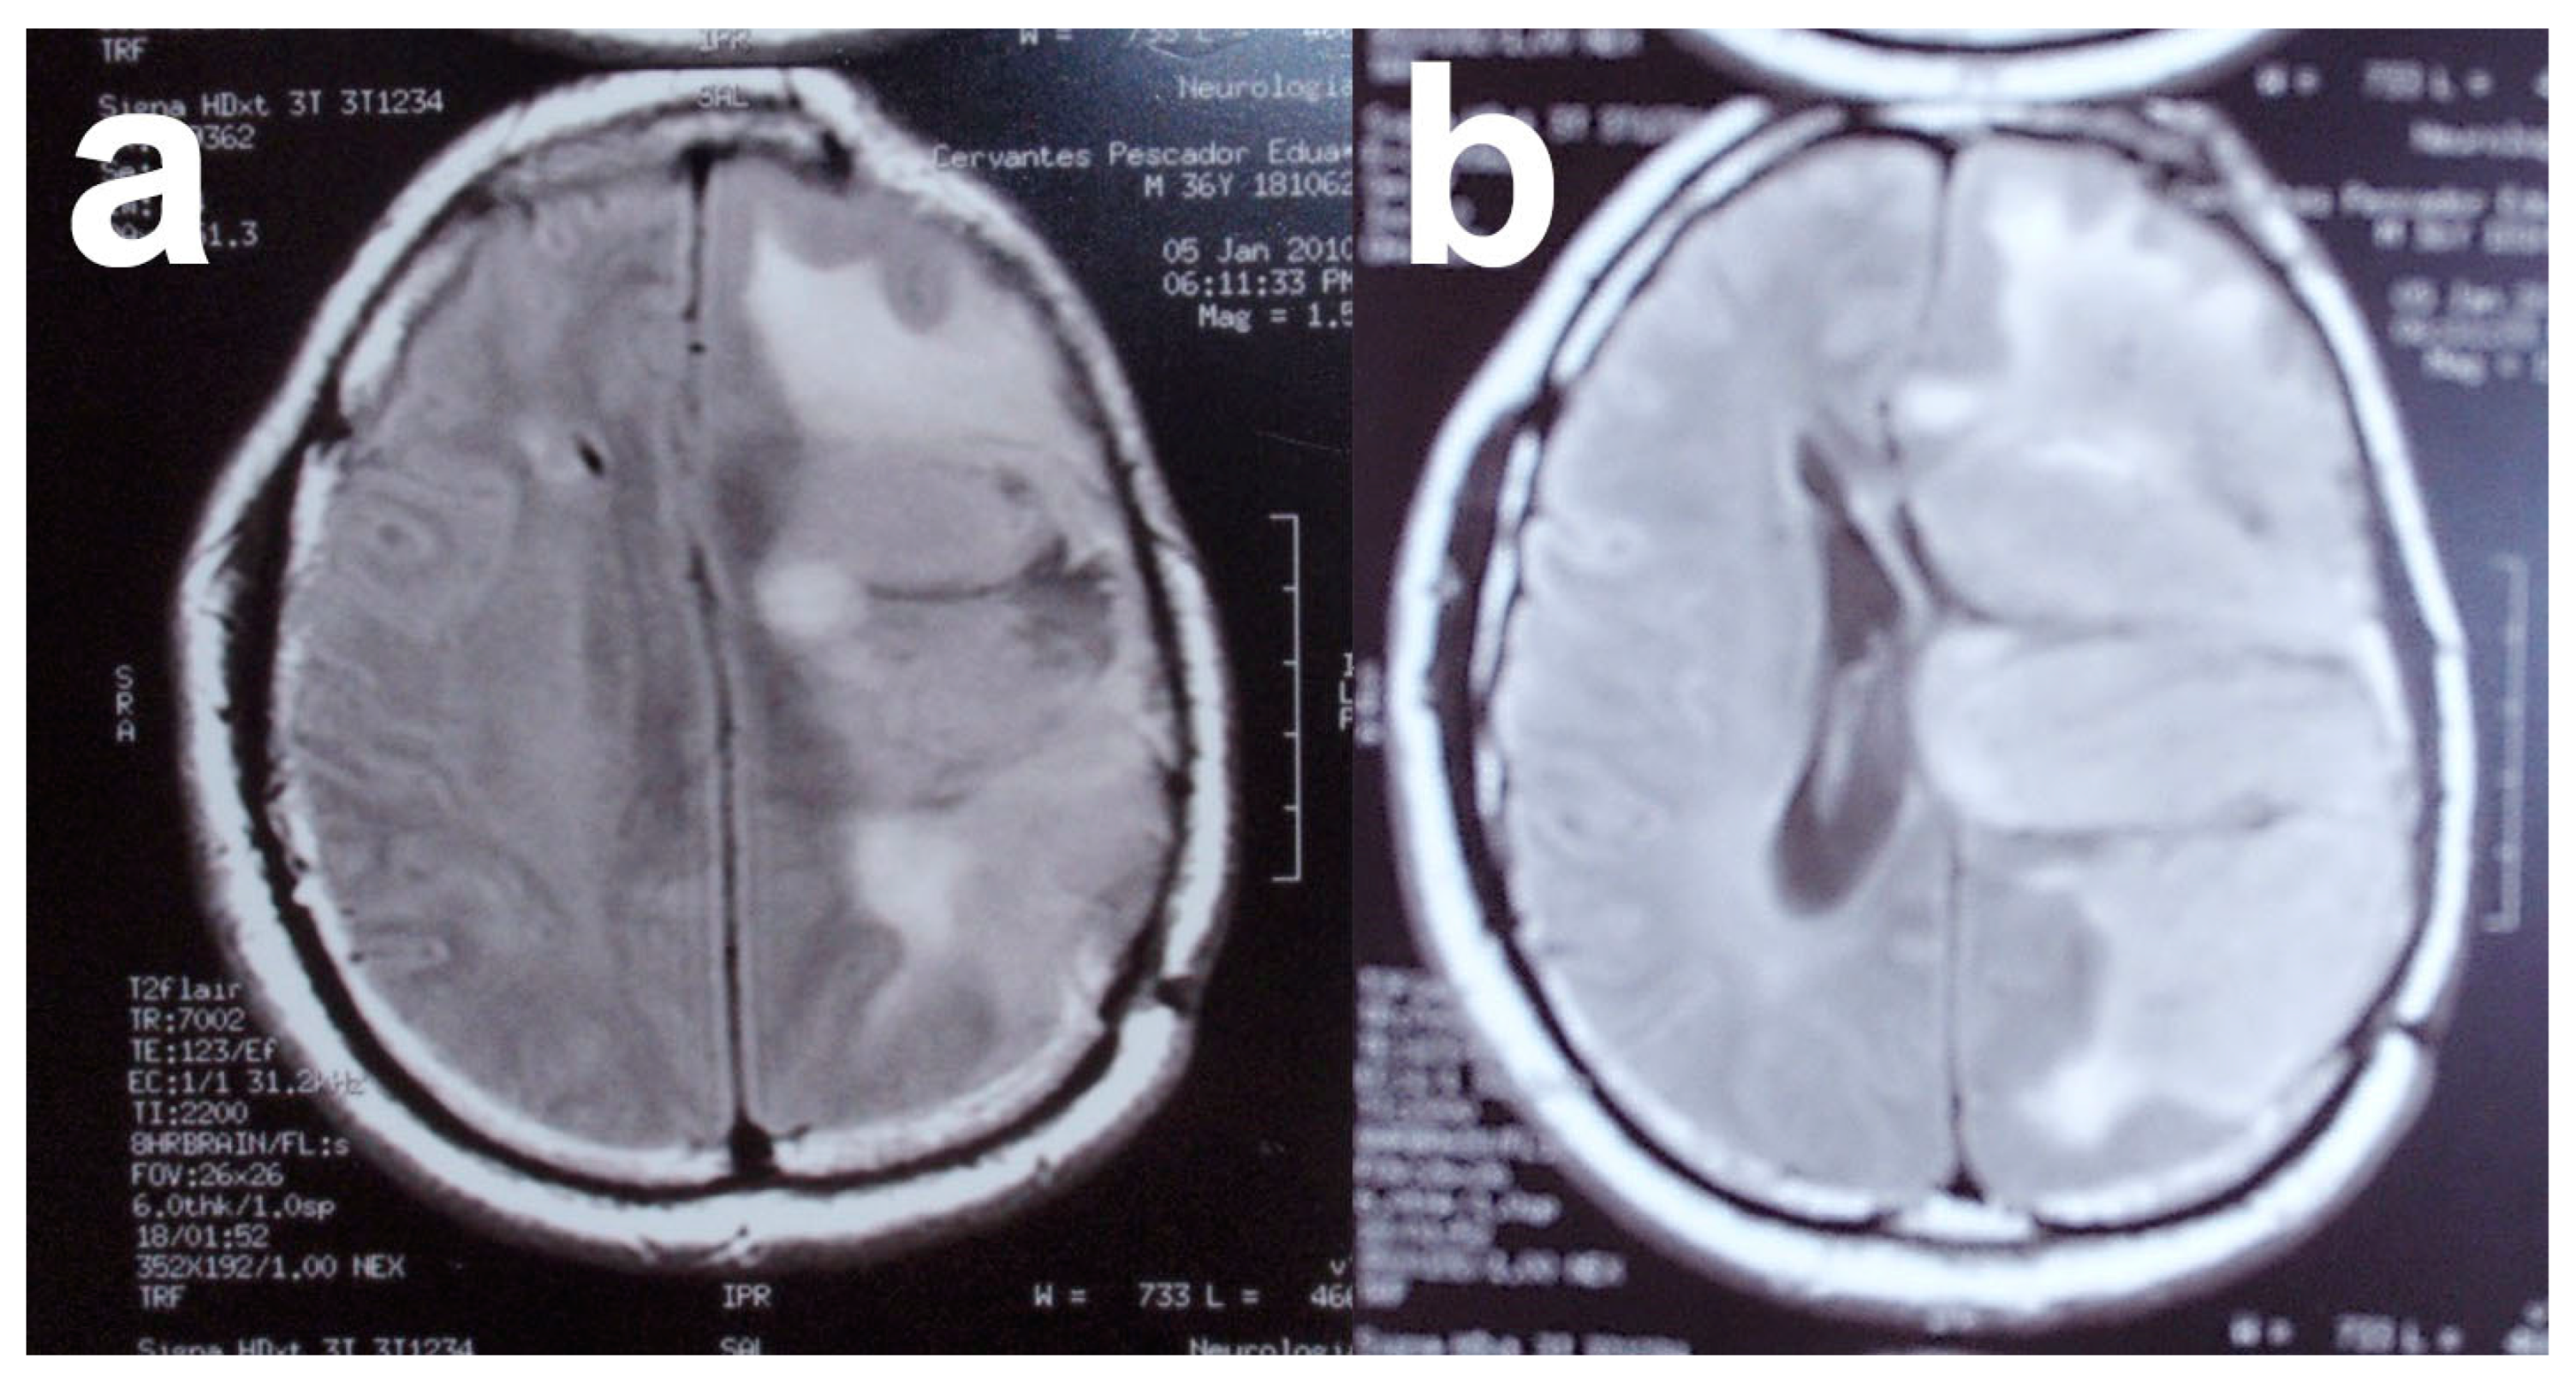

4.1. Clinical Story

4.2. Treatment

4.4. Results and Prognosis